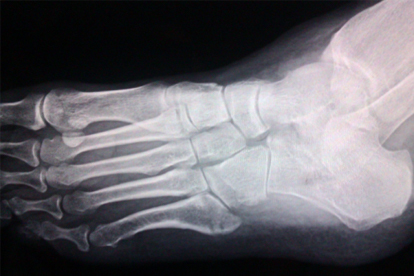

脚骨折期间通常不建议饮酒,酒精可能影响骨骼愈合过程并增加并发症风险。

酒精摄入可能干扰骨骼的自然修复机制。骨折愈合依赖充足的血液供应输送营养与氧气,酒精具有血管扩张作用,短期可能增加局部血流量,但长期或大量饮用会导致血管收缩,减少骨折端血供。酒精还会抑制成骨细胞活性,这是负责新骨形成的关键细胞,其功能受损会直接延缓愈合速度。酒精可能影响钙与维生素D代谢,这两种营养素对骨骼mineralization至关重要。饮酒后平衡能力下降,可能造成患肢意外负重或摔倒,导致骨折移位或内固定失效。酒精与部分镇痛药物存在相互作用,可能增强药物副作用或降低疗效。